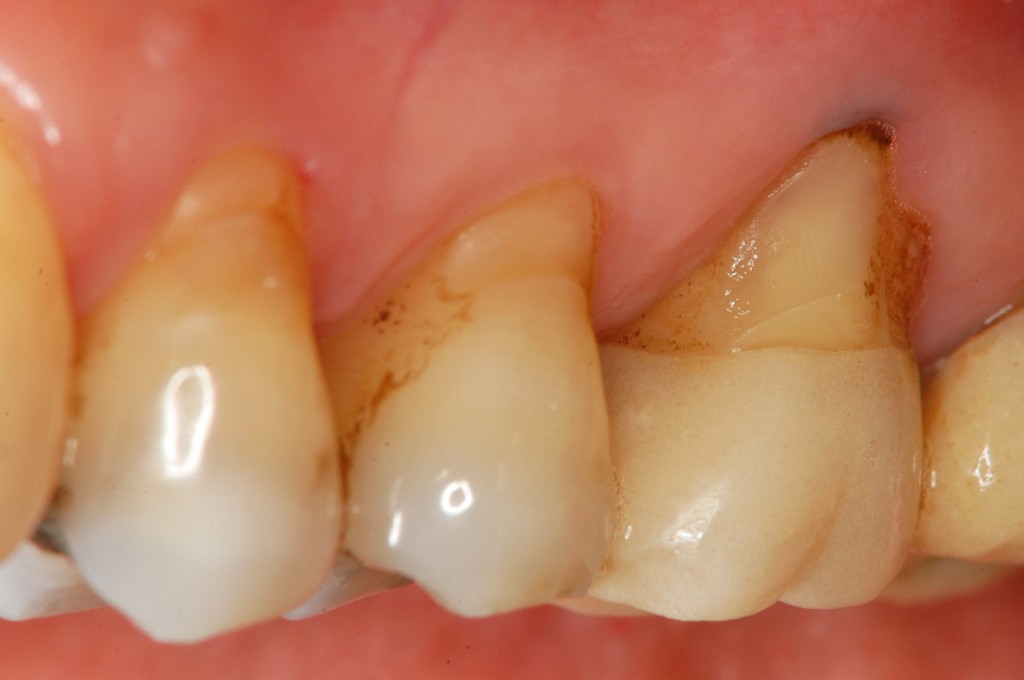

• 治療後

上の奥歯の歯茎がやせていて,根っこが見えている状態です。治療法はエムドゲインと結合組織移植を用いた根面被覆術を選択しました。

治癒後の写真は,このページ一番上の治療後の写真をご覧ください。

術前に比較して,露出していた根っこの面積が少なくなっているのがわかります。ご本人も大変喜ばれていました。